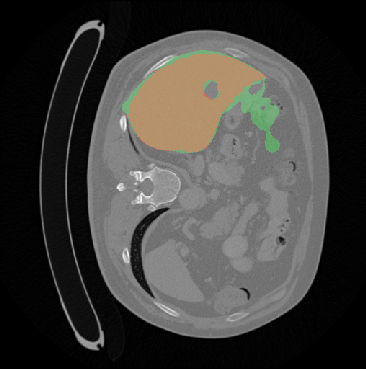

Each pixel of the image is assigned to one of the two classes liver/other tissue and tumor/other tissue, respectively, with a certain probability. Results of the automated liver and tumor segmentation are visualized in Figure 3.2. Comparison with ground truth and segmented liver and tumor give rise to the assumption that our approach is highly promising for obtaining high performance metrics. To qualitatively evaluate performance, we applied some of the commonly used evaluation metrics in semantic image segmentation. Performance metrics are summarized in Table 1.

We evaluate this model under usage of test and validation set from LiTS-Challenge and Innsbruck data ( images). The evaluation metrics are summarized in Table 1. The liver segmentation evaluation scores indicate that our models, especially perform remarkable good, provided that the sequential approach outperforms the One-Step method primarily in the tumor segmentation task. in Pixel accuracy, Intersection over union (IoU) and Rand Index (RI) have values very close to . IoU and Rand Index performance score of the tumor segmentation show that the application of balanced loss with , achieves the best results.